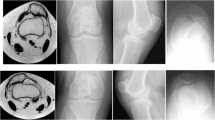

In order to create a prosthesis that is biomechanically and anatomically adapted to the rat knee joint, the same methods employed in human clinic were used. Briefly, collected tibial and femoral bones were immersed during 4 hours in boiling water with antibacterial soap in order to completely separate bones from surrounding tissue. Bones were digitalized using an optical measuring system (3D Scanner ATOS 3, GOM®, Braunschweig, Germany) and the data were treated by an inverse engineering methodology of a computer-assisted design system (CATIA V5, Dassault System®, Velizy, France). Thus, three-dimensional (3D) numerical model of rat knee joint was obtained. From this model, a computer-assisted design system allowed to design the geometrically-adapted tibial and femoral components of the future prosthesis (Fig. 1). Femoral and tibial components were respectively machined from a titanium alloy (Ti6Al4V) and a polymer material (polyether-ether-ketone; PEEK) by a 5-axes micro-milling machine (US 20, DMG-Mori®, Leonberg, Germany). The programming process for machining each piece was performed by an ISO standard program generated by the CATIA V5 system.

Total knee prosthesis. (A) Rat tibial and femoral bones are three-dimensionally modeled and components of the total knee prosthesis are designed. (B) Photographs of the total knee prosthesis: front (upper) and profile (lower) views. (C) Full design of the prosthesis positioned between the tibial and the femoral bones.